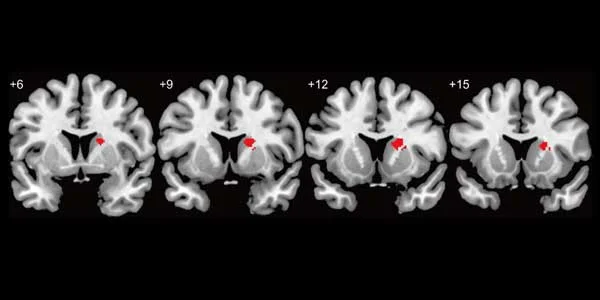

Areas of the brian that are associated with being in love. (Kawamichi et al., 2016 Fig. 2, altered for artistic purposes)

A fancy pants science technique that images brain functions, Functional Magnetic Resonance Imaging (fMRI), shows that the same regions of the brain “light up” for romantic love and addiction. These regions are part of the “reward system” which is known as the “dopamine-rich regions”. Dopamine, a hormone, is highly active within the reward system to give you that oh-so good feeling. But is the addiction during romantic love chemical or behavioral? Women and men who were scanned with fMRI revealed that they were passionately in love, and reward areas of their brain responded differently to liking (seeing a hot guy/girl) and wanting (loving a guy/girl) someone. Also, people in committed relationships are less likely to seek side action and also view others as less attractive than they really are.